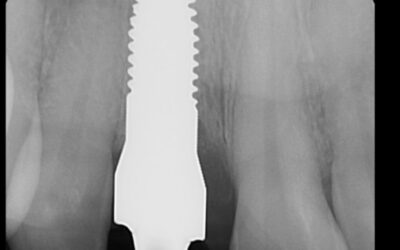

Zirconia Implants vs. Titanium Implants: What’s the Difference?

Zirconia Implants vs. Titanium Implants: What’s the Difference?When considering dental implants, patients are faced with numerous decisions—including choosing between titanium and zirconia implants. These two materials differ in composition, performance, aesthetics,...